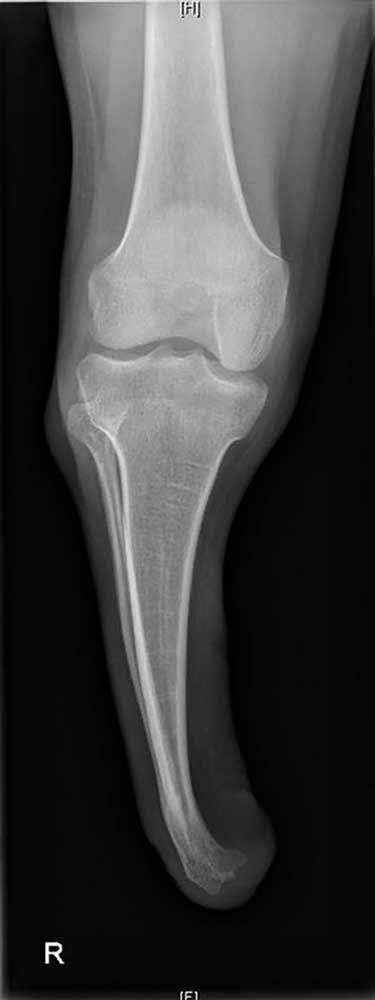

Ein 12-jähriger Patient weist eine Unterschenkel-Dysmelie und eine Varusfehlstellung des Stumpfes auf. Im Alter von 13 Jahren wurden eine Epiphyseodese der proximalen lateralen Tibia und eine Fibula-Epiphyse durchgeführt (Abb. 1a). Nach Wachstumsabschluss zeigt sich weiterhin eine varische Unterschenkelachse, insbesondere im distalen Anteil (Abb. 1b). Die Beinachse kann zwar durch die orthoprothetische Versorgung bzw. den korrekten Aufbau berücksichtigt werden, es entsteht jedoch rezidivierend eine Druckstelle am Stumpfpol sowie lateral an der proximalen Fibula durch mechanische Überbelastung (Abb. 1c). Daraus resultieren massive funktionelle Einschränkungen und letztlich die Indikation zur Stumpfrevision; dadurch kann die mechanische Belastung auf den Stumpf reduziert und gleichzeitig funktionell die Beinachse korrigiert werden.